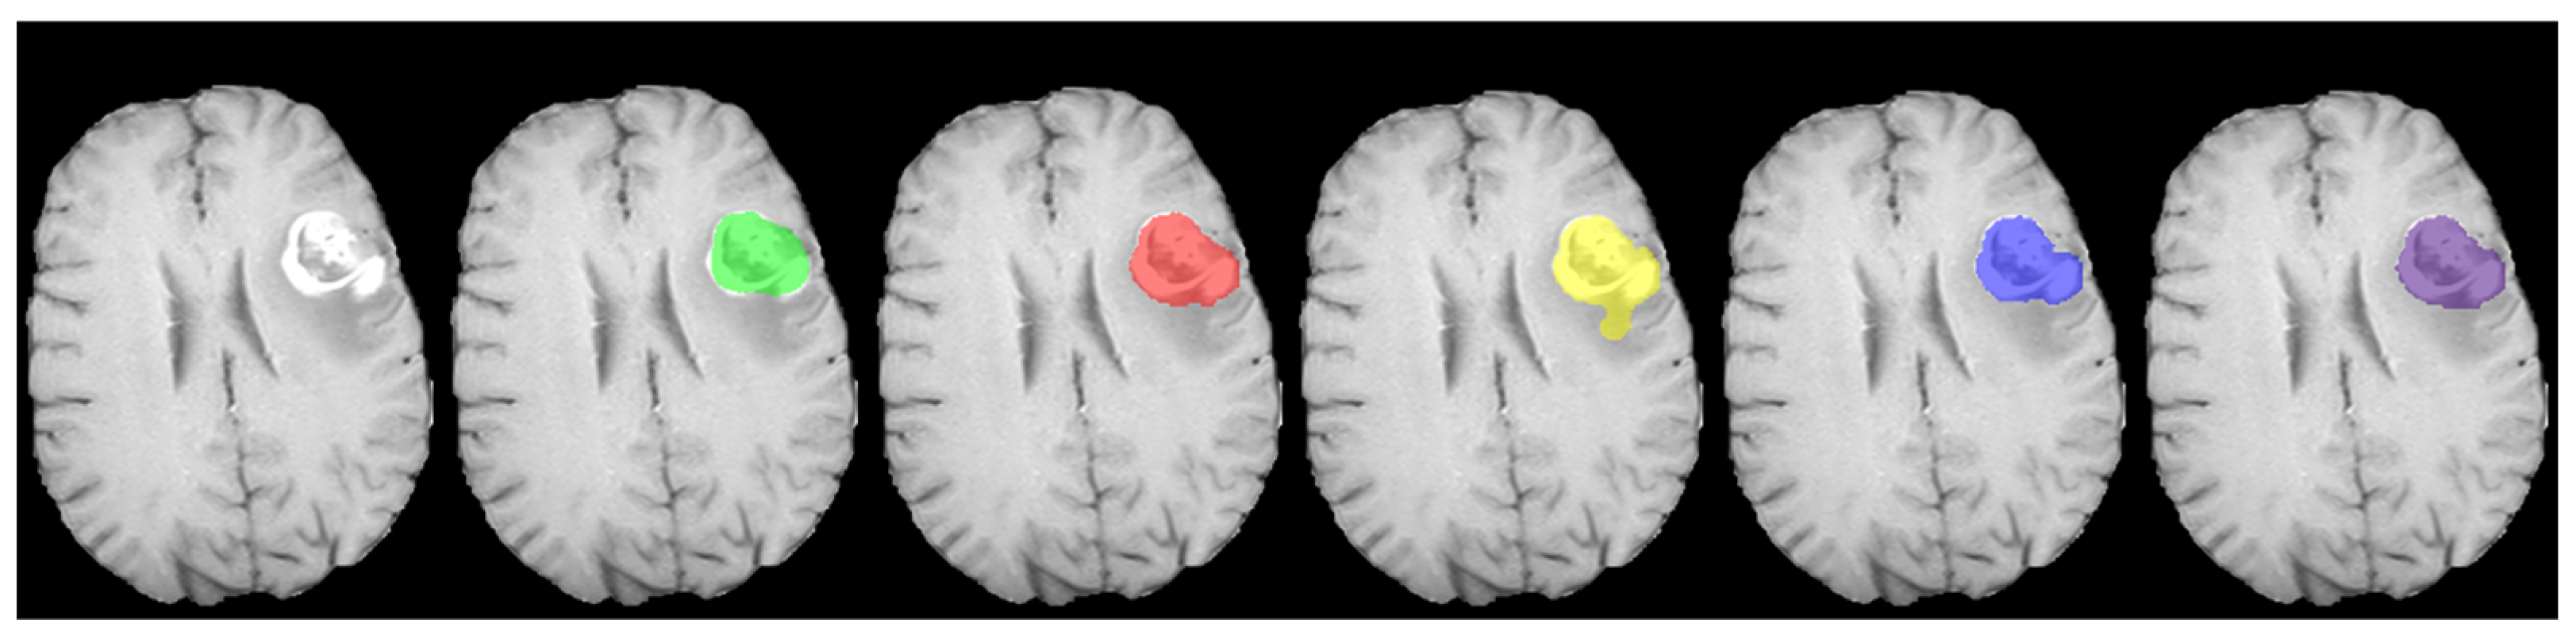

4.4. Validating RFS+ on Local Dataset